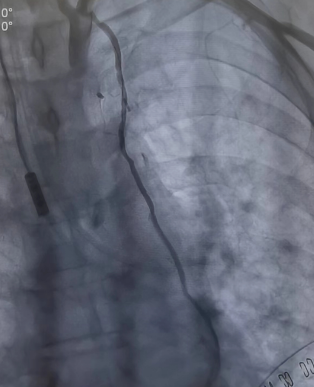

將兩者結(jié)合的手術(shù)方式就是雜交技術(shù)即“一站式微創(chuàng)”手術(shù)。手術(shù)先在左側(cè)胸壁做一個(gè)5-7厘米切口,進(jìn)行左胸廓內(nèi)動(dòng)脈-左前降支(LIMA-LDA)架橋。接著進(jìn)行冠脈造影,檢查LIMA-LDA橋血管通暢度。同時(shí)在冠脈其他狹窄部位放入冠脈支架。

同期進(jìn)行冠脈放支架(檢查LIMA橋血管通暢)